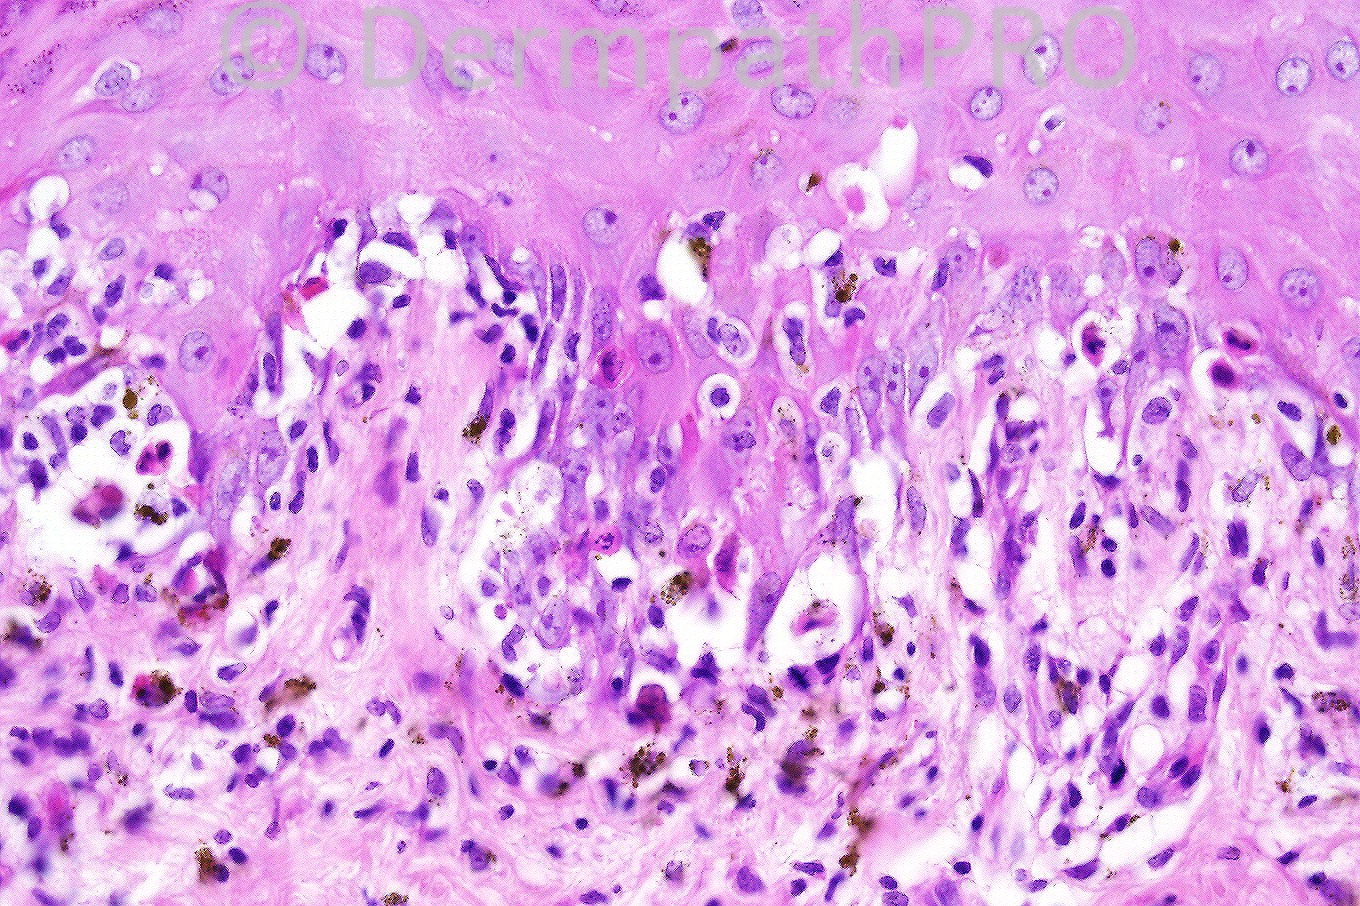

Female 35 years who presented with erythematous lesions. Past history of herpes infection.